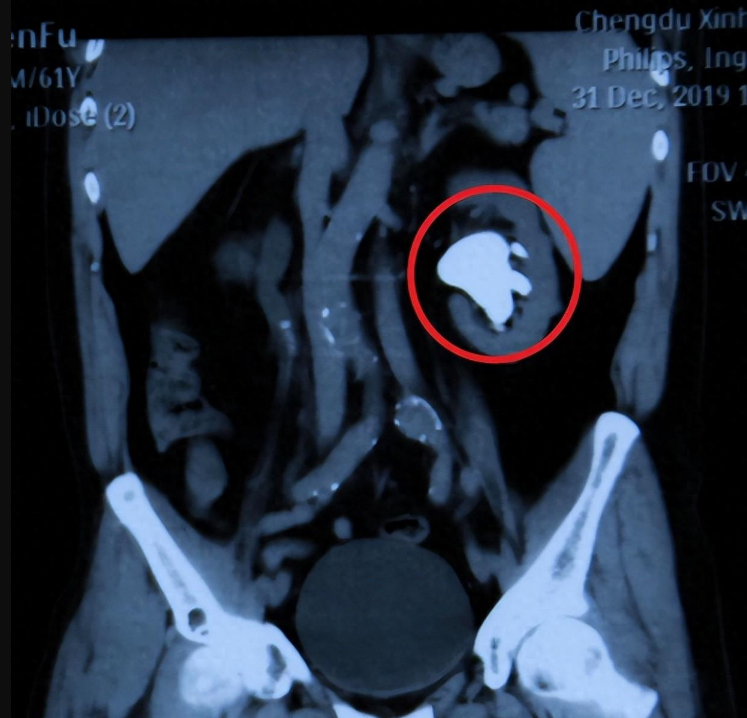

王先生的X光片赫然可见一个白色空洞

四川结石病医院泌尿外科孙剑鸿主任作为其主治医生为患者进行了详细检查,结果显示:患者左肾内现高密度阴影,结石几乎占据了大半个肾脏,在x光片上呈现出骇然的白色空洞。